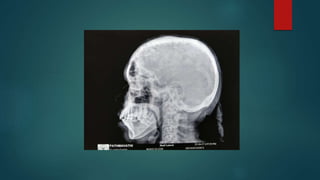

Skull

osteitis circumscripta or cotton wool exudates

tam o' shanter sign

widening of the diploic space and an

overall enlargement of the cranium

Skull osteitis circumscripta orcotton wool exudates

tam o' shantersign widening of the diploic space and an overall enlargement of the cranium